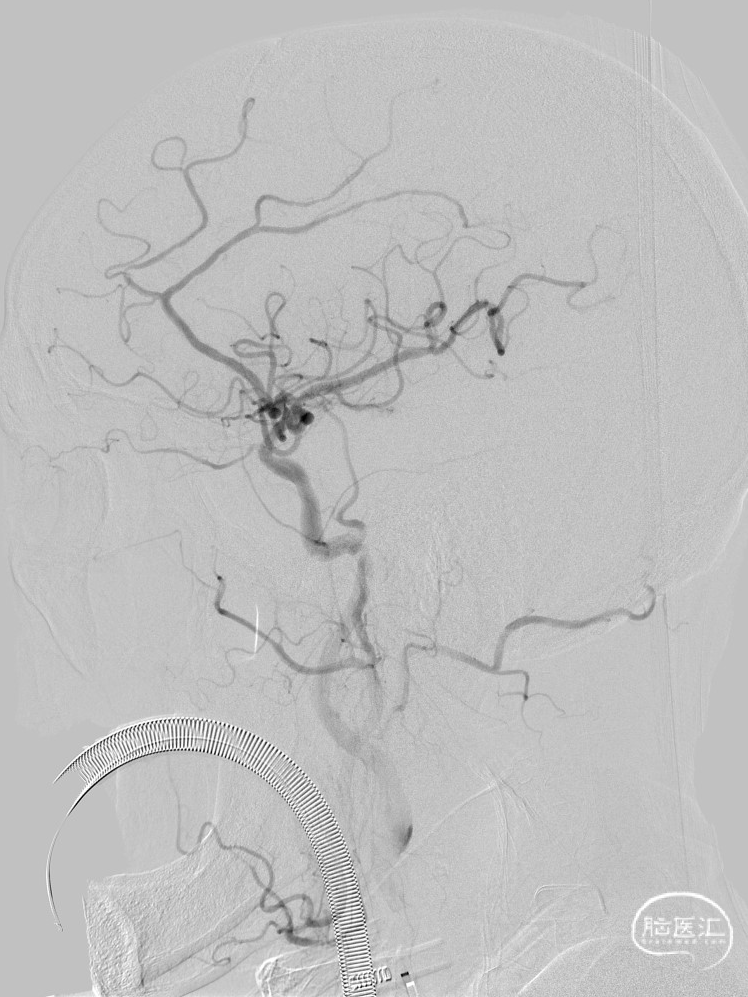

DSA检查提示左侧大脑中动脉上干闭塞

术后即刻影像,M2段远端血流mTICI 3级,动脉瘤内造影剂滞留。

复查CT及CTP:未见出血及低灌注区。